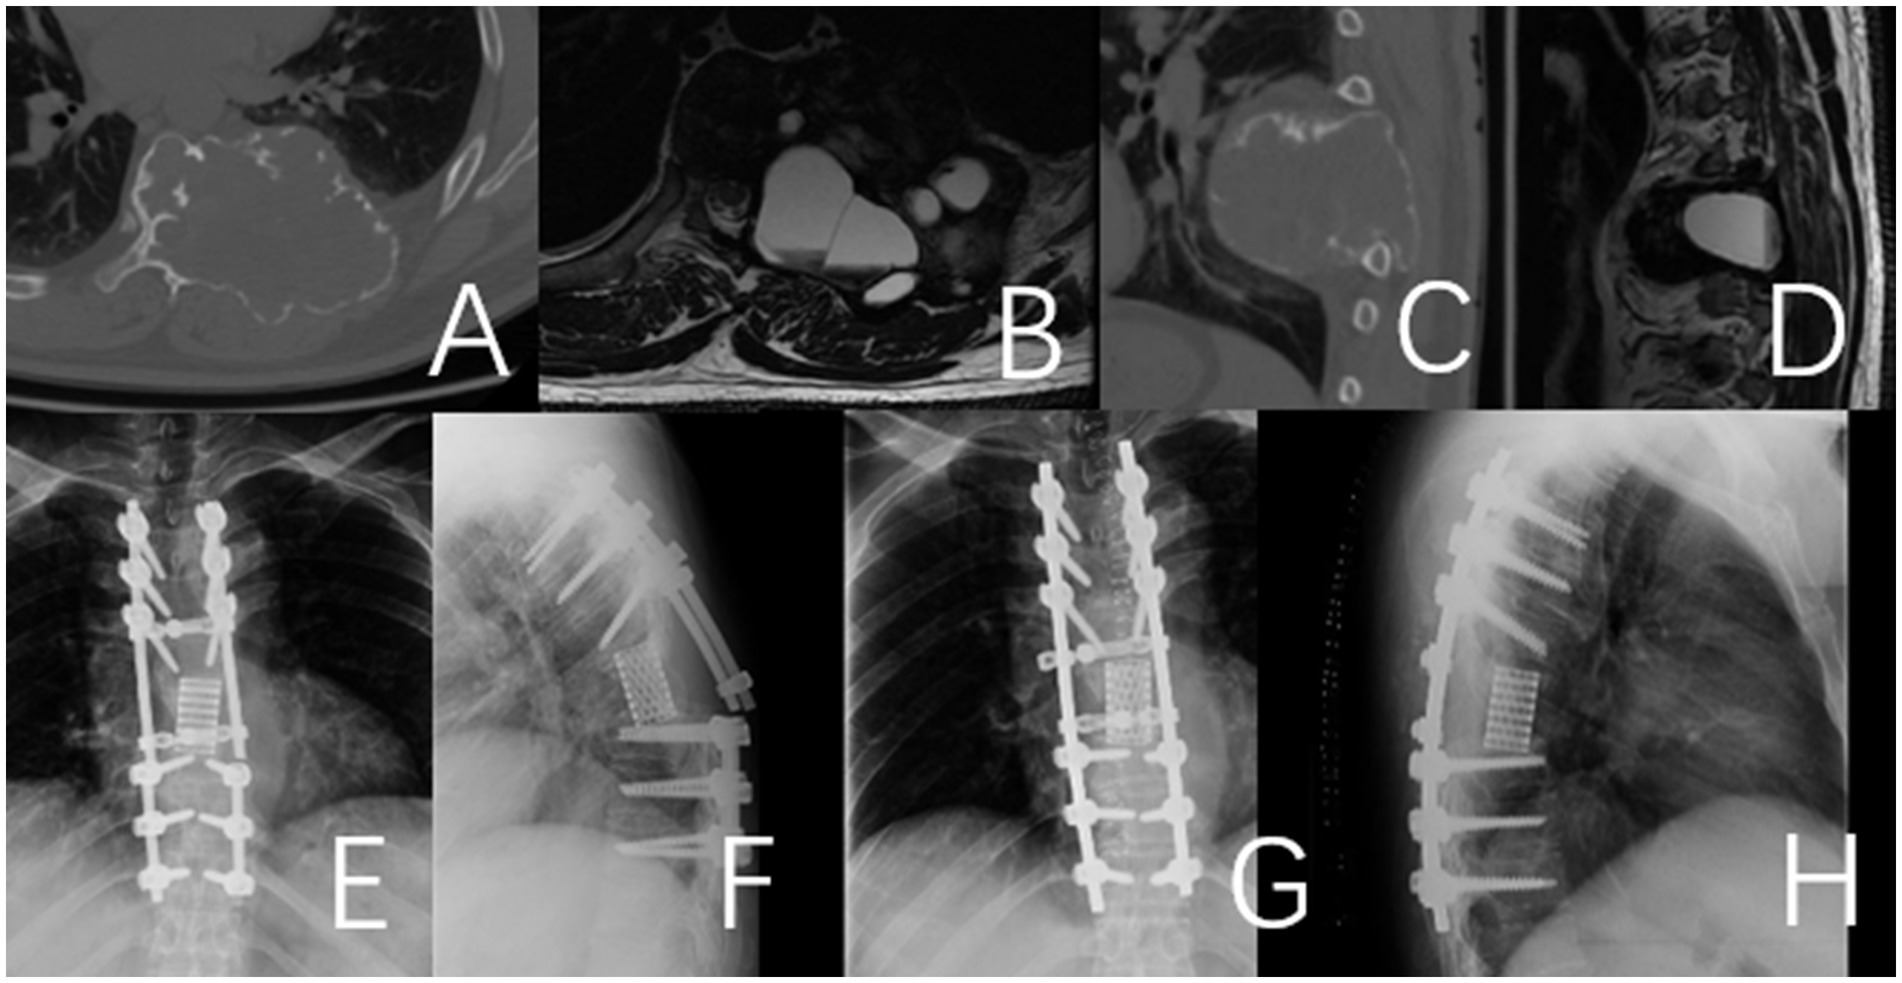

Figure 1. This case involves a 50-year-old female patient with a T11 giant cell tumor, classified under the WBB staging system as T11 1–10 (A–D). The patient received denosumab treatment for 3 months prior to undergoing staged T11 en bloc resection surgery, during which a 3D-printed artificial vertebra was implanted between T10 and T12, and subsequently fixed. During the surgery, tumor operations were executed while cutting both sides of the pedicles. During posterior approach surgery, a tear in the right pleura resulted in pleural effusion, which was resolved with adequate drainage, leading to a full recovery. (A–D) Preoperative CT and MRI images revealed a large mass in the thoracic cavity formed by the T11 vertebral tumor. (E) Second-phase anterolateral approach surgery. (G) Specimen of the second phase surgery. (F) Specimen of the first phase posterior surgery. (H) CT images of the T11 vertebra and tumor excised during the second-stage surgery. (I,J) Imaging at the 4-year postoperative follow-up indicated that the internal fixation was well positioned and showed no evidence of tumor recurrence.